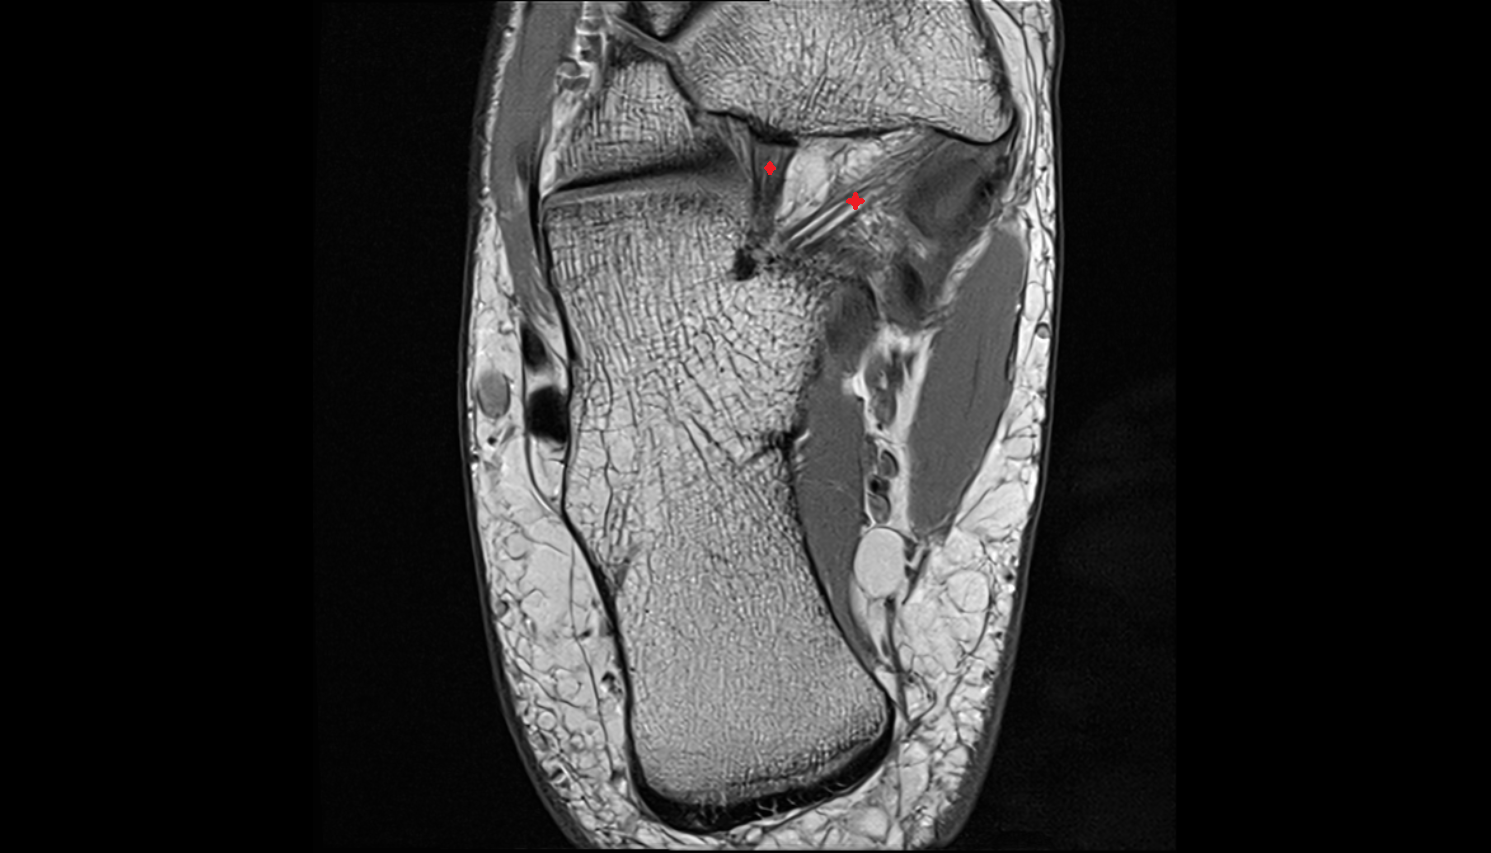

- Ankle joint

- Talus

- Calcaneus

- Medial malleolus

- Lateral malleolus